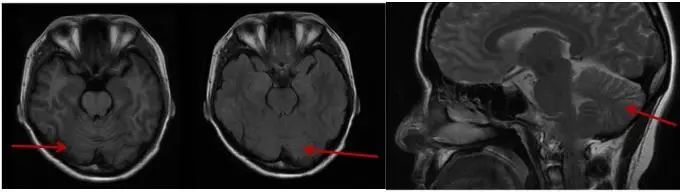

1.2 家系调查 见家系图谱(图3),先证者之父约70岁发病,症状相似,具体无法追溯,因他病亡故。先证者之女尚无临床症状,头颅MRI小脑无明显萎缩(图4),查基因检测提示CACNA1A CAG重复次数为 22 次(图5),在全突变范围内。

图4 患者之女MRI T1、T2及矢状位图Fig.4 MRI T1, T2 and sagittal maps of patient’s daughter, 2023

SCA6型在我国属于较为少见分型(约1.7%),该病临床特征为成年发病、缓慢进展的小脑共济失调、构音障碍和眼球震颤,发病年龄19~73岁,随病情发展可出现吞咽困难和窒息[4],病理特点为小脑萎缩而无脑干萎缩。本例患者首发症状为言语含糊伴行走不稳,随后逐渐进展出现头晕、饮水呛咳、眼球震颤等症状,属临床症状较为典型病例,头颅MRI见小脑明显萎缩。其父发病具体年龄无法追溯,据先证者言约70岁发病,症状相似,其女27岁,为无症状基因携带者,此家系暂符合遗传早现现象,但因病例数少,且其女尚未发病,还需进一步追踪验证。